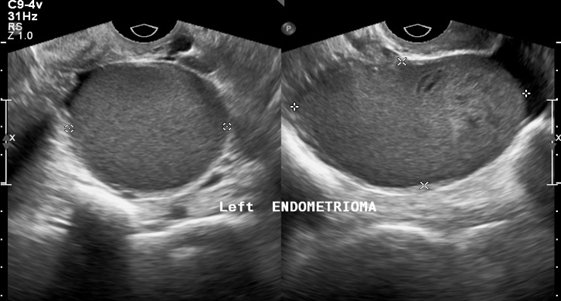

In patients without endometriosis, the average longitudinal measurement of the uterus was 7.5cm with a range of 5cm to 8.5cm and the average transverse measurement was 5.0cm with a range of 4.5cm-6.4cm (Figure 1).26 In the presence of endometriosis, this size increased depending on the size and site of the endometrioma. The Figure 2 shows dilation of the uterine cavity due to the presence of endometrioma. In this patient, the transverse measurement increased to 6.5cm (Figures 3a & 3b).

Figure 3a An ultrasound image of the uterus showing left endometrioma. The dots indicate size of masses present.

Figure 3b An ultrasound image of the uterus showing right endometrioma. The dots indicate size of masses present.